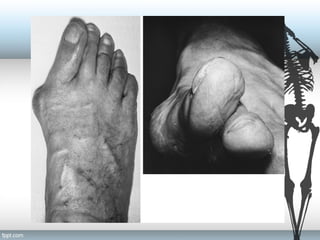

Clinical Presentation

PAIN over the medial eminence (Bunion).

• Pressure from footwear is the most frequent cause of

this discomfort.

• Bursal inflammation

• Irritation of the skin

• Breakdown of the skin may be noted.

• Bunion consists of:

• Bony exostosis / prominence of the metatarsal head

• Overlying subcutaneous bursa

• Hyperkeratosis of dermis

Signs and Symptoms

• Asymptomatic

• Pain- The primary

symptom of hallux

valgus is PAIN over the

medial eminence.

• Pressure from footwear

is the most frequent

cause of this

discomfort.

• deformity

• Tenderness

• Aesthetic